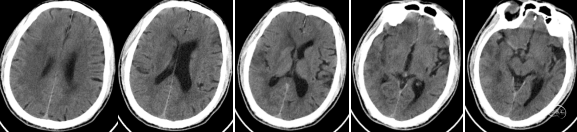

急诊绿色通道完善脑MR:1.右侧额顶叶、基底节区、岛叶、颞枕叶多发急性期梗死;2.右侧大脑中动脉重度狭窄或闭塞。

术后第二天复查脑CT示右侧额颞叶及基底节区梗塞。